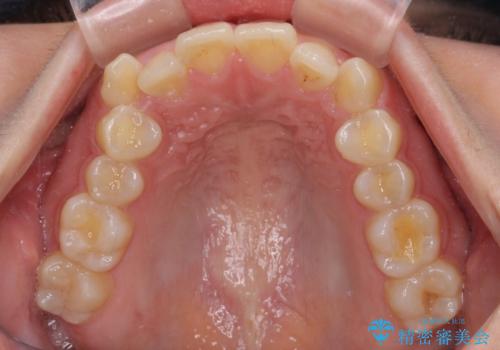

八重歯を治す 非抜歯のワイヤー矯正治療

- 左右の八重歯を気にして来院された患者様です。

ワイヤー装置でもマウスピースでも対応可能な歯列でしたが、マウスピース矯正は自己管理が煩わしいとのことでワイヤー矯正を選択されました。

八重歯である犬歯は歯根が長いため、上顎前歯が出っ歯になるリスクがあるため、必要に応じてアンカースクリューを用いて奥歯を後方に移動させる可能性をお伝えしました。